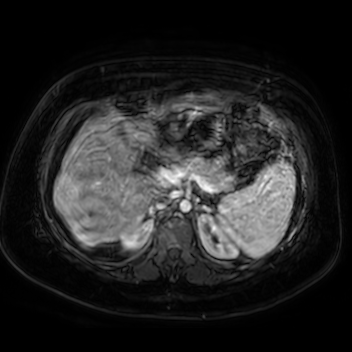

69 M with PMH of HCV cirrhosis & HCC s/p resection in 14 years ago presenting today for a screening ultrasound.

135/73 mmHg / 78 bpm / 16 breaths/min / 96.4°F

sclerae anicteric, no jaundice

CMP wnl, AFP 5